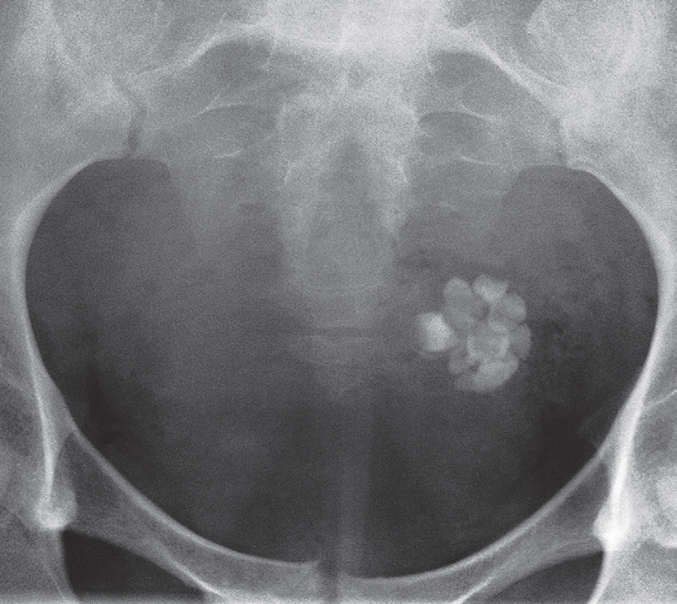

Plain film showing well-developed teeth within the cyst